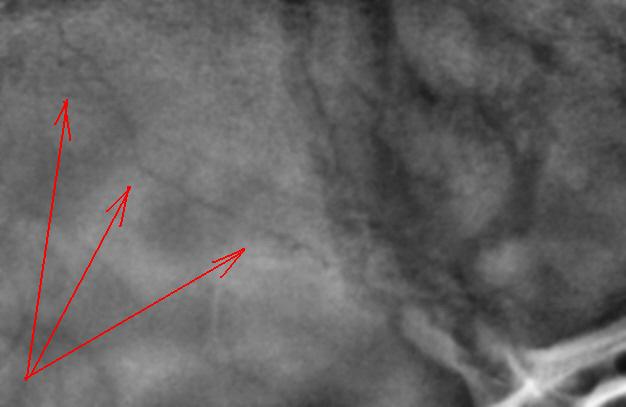

На боковой рентгенограмме нуждаются во внимании, на мой взгляд, помеченные стрелками "линии".

Провокация № 2. Чем объясним эту линию просветления?